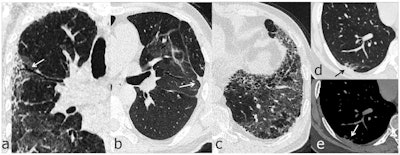

To address this knowledge gap, Han's group assessed pulmonary sequelae on six-month follow-up chest CT scans in 114 patients who survived severe COVID-19 (all patients underwent chest CT at symptom onset). Lung changes included opacification, consolidation, reticulation, and fibrotic changes.

The investigators found that 35% of the study participants (40 of 114) went on to develop lung changes within six months. Patients with the following factors at disease onset were at higher risk of manifesting signs of lung damage at six-month follow-up:

"Whether or not these fibrotic-like changes, found at six months, reflect permanent change in the lung remains to be investigated," the authors noted.